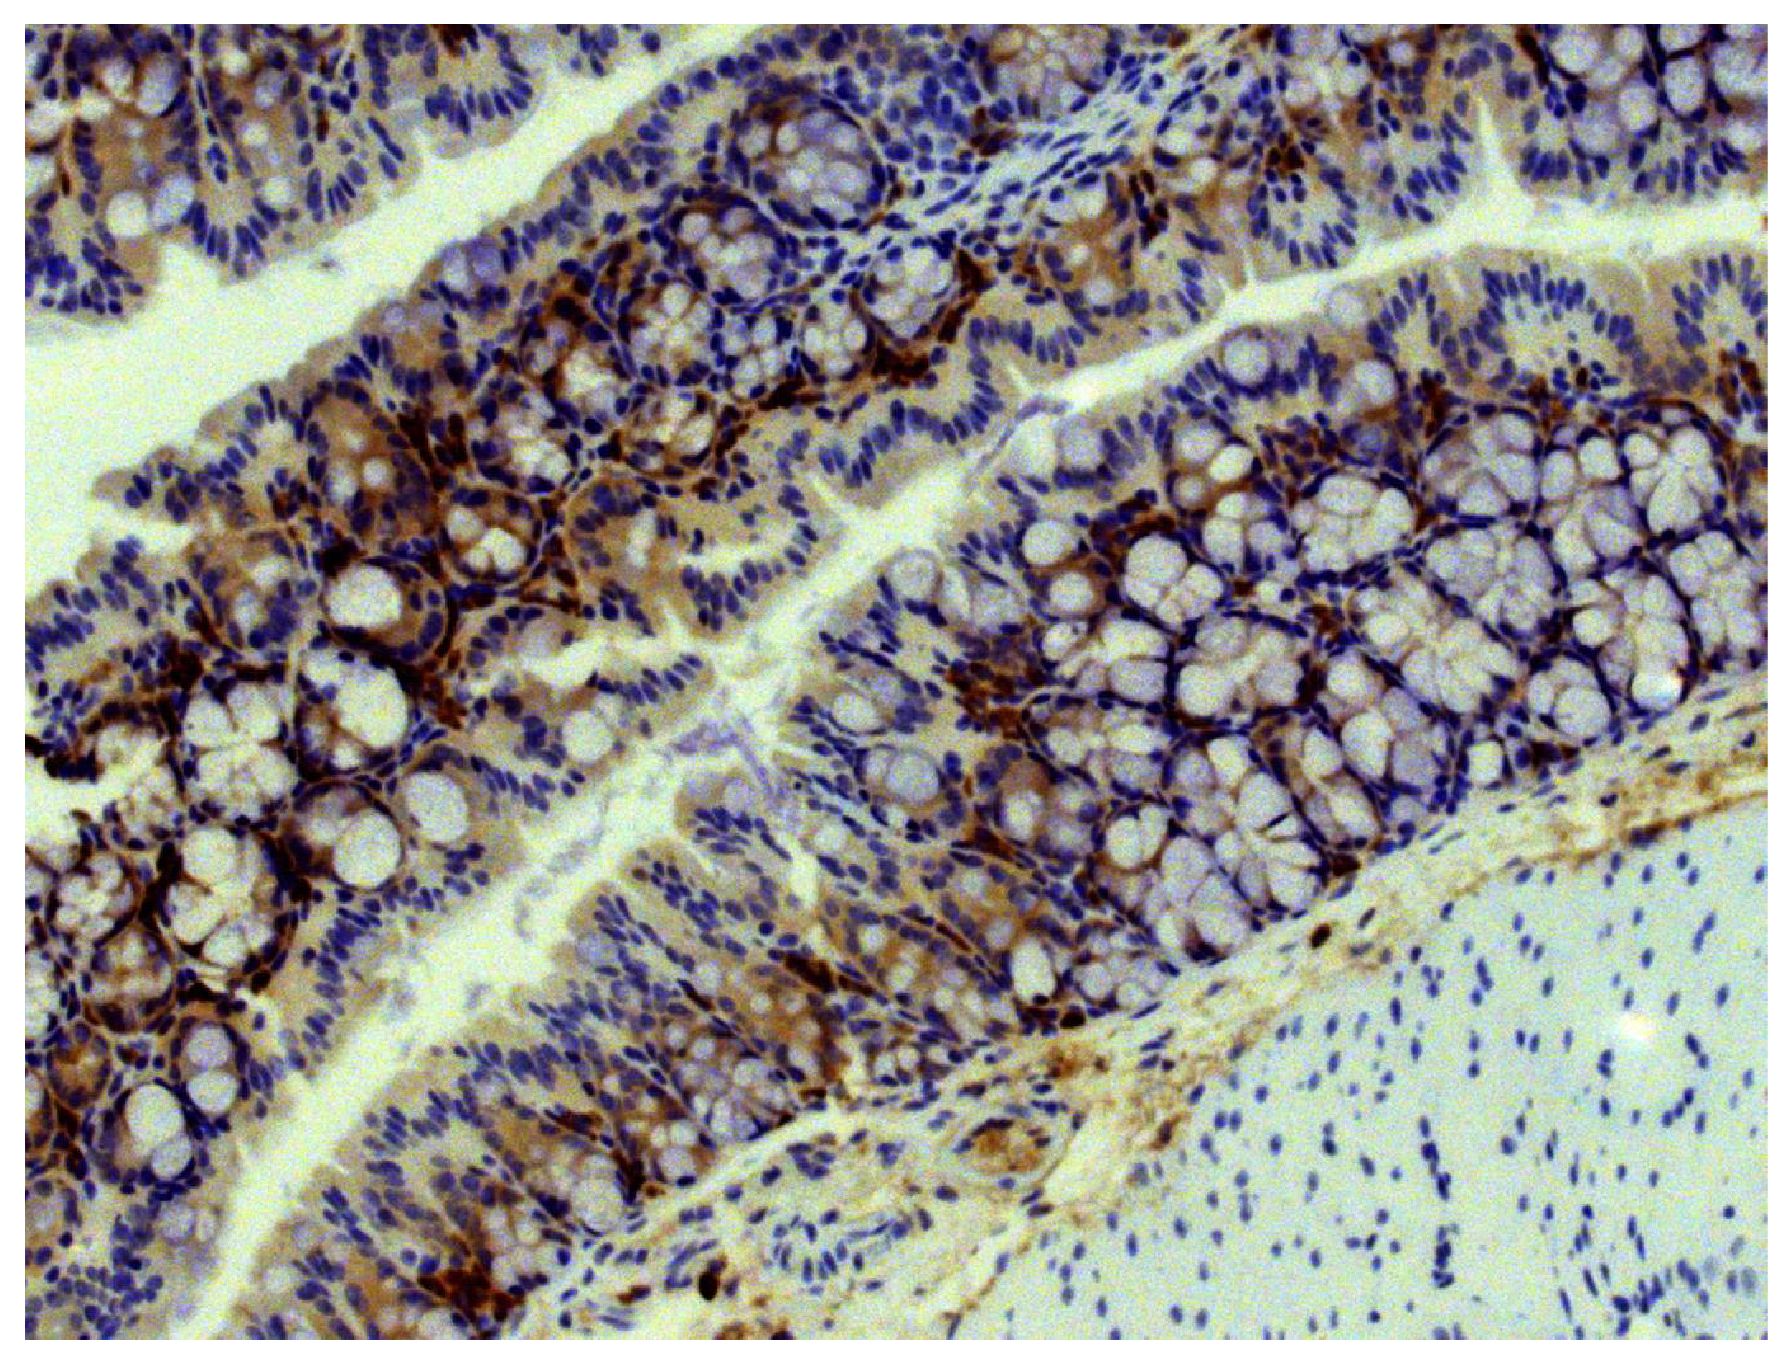

Paraffin embedded BALB/c mouse colon tissue section was stained with Goat Anti-Mouse IgA-HRP (SB Cat. No. 1040-05) followed by hematoxylin and DAB